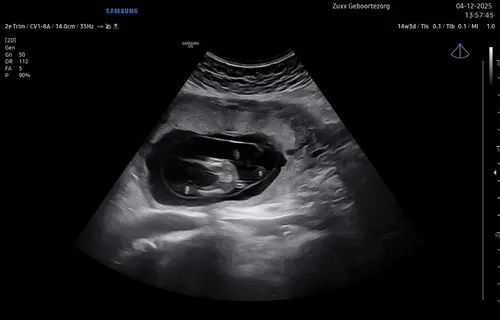

Hier met 14+3. Ook zwanger van een dochtertje nadat ik 5 jaar geleden een dochtertje ben verloren en daarna 2 gezonde jongens heb gehad. Ik snap het gevoel van onwerkelijk.